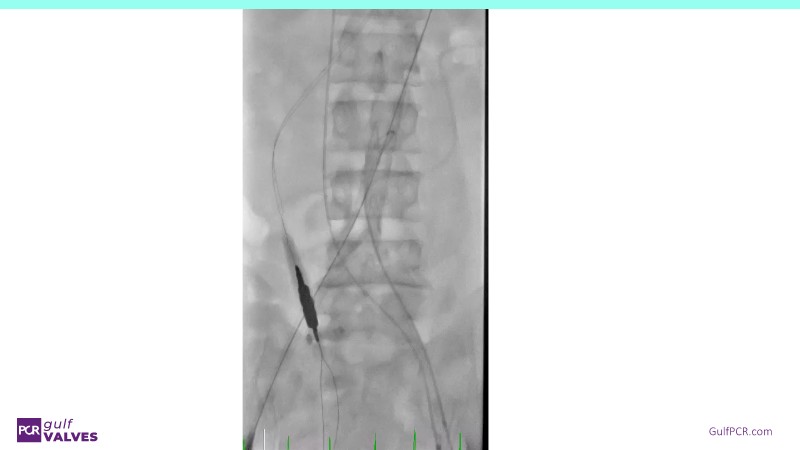

Discover a selection of cases showcasing the key features of the Navitor Valve System and its clinical applications. This session explores auxiliary access, the use of Navitor in alternative access and complex PCI, its performance in challenging peripheral anatomies, and innovative outcomes with the Vantage 30D system.